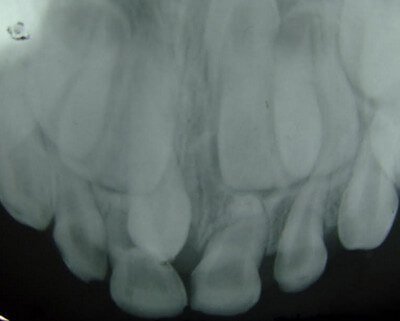

Picture 3: Supernumerary teeth on the lower jaw.

Image Source: drsteakley.com